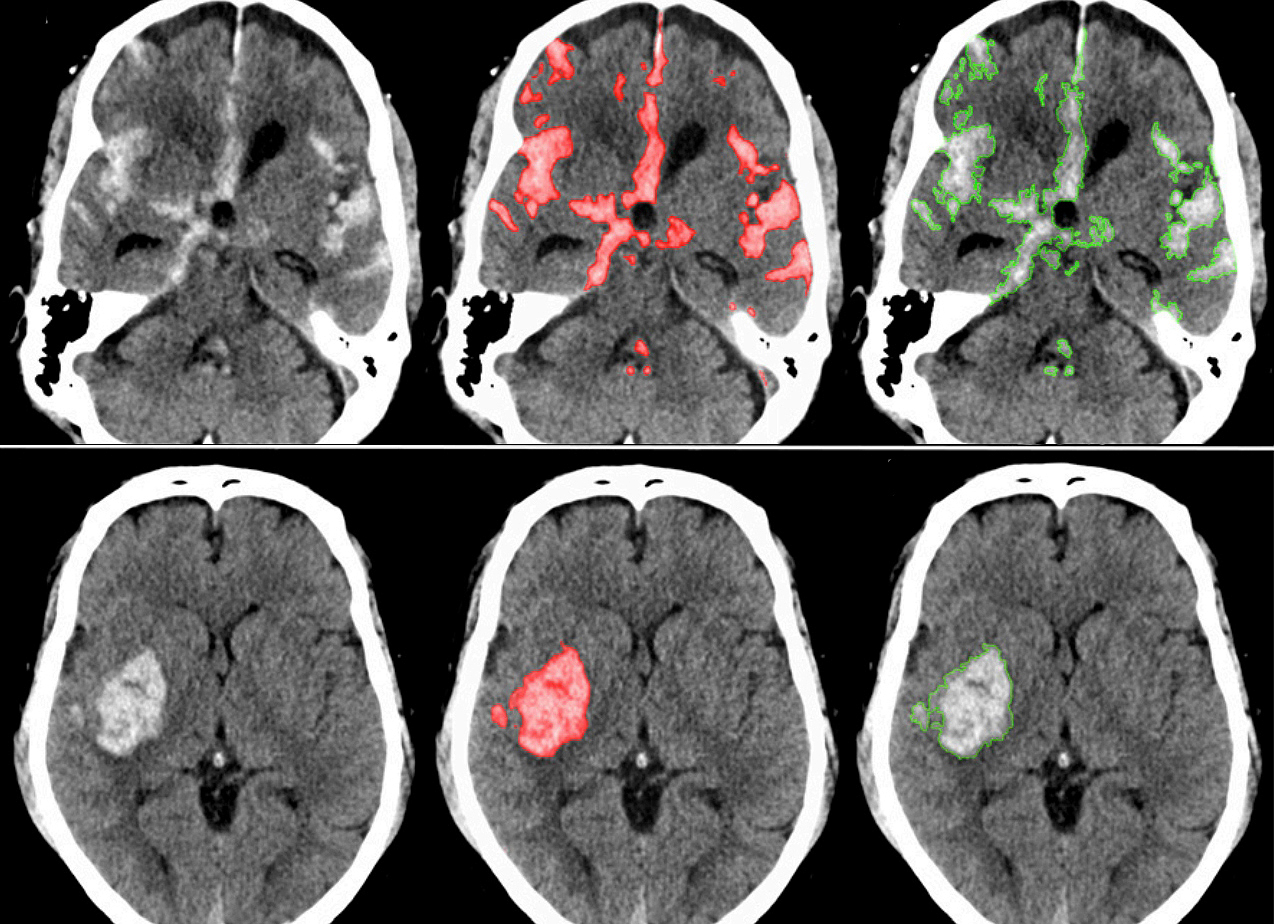

1. 뇌출혈, 우리 몸에 무슨 일이 생기는 걸까요?

뇌출혈의 발생을 시각화한 이미지

뇌출혈은 뇌 속 혈관이 터져서 피가 나는 질환을 말합니다. 뇌졸중 환자 10명 중 1명 정도가 뇌출혈 진단을 받는다고 합니다. 뇌출혈은 뇌경색과 다르게 특별한 전조 증상이 거의 없다는 것이 특징입니다.

갑자기 발생하며, 그 즉시 심각한 후유증을 남길 수 있어 무엇보다 미리 대비하고 빠르게 대처하는 것이 중요합니다. 뇌출혈은 뇌에 큰 손상을 줄 수 있기 때문에 이 질환에 대해 잘 알아두는 것이 좋습니다.

뇌출혈은 뇌혈관이 파열되어 뇌 안에 출혈이 발생하는 질환입니다. 갑작스럽게 발생하며, 예방과 조기 대응이 매우 중요합니다.